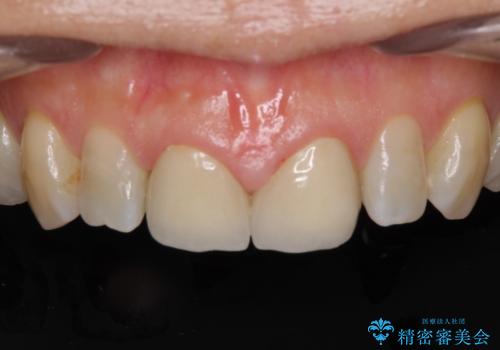

前歯のすきっぱ&奥歯の虫歯 セラミッククラウンで徹底的に治す

- 前歯のすきっぱを主訴にご来院された患者様です。他院でつめものやラミネートべニア(前歯の表面のみセラミックを貼り付ける)を行っていましたが、頻繁に外れることに悩まれており、クラウン(歯全体をセラミックがつつむ)をご希望されました。また、奥歯に大きな虫歯があり、歯が割れていたため、奥歯の治療も併せて行いました。

今回はまず欠けた場所を修復して見た目を回復させたのち、ラミネートべニアの仮歯をつくり、しばらく使用して考えて頂きました。メリットやデメリットを説明した結果、外れにくいセラミッククラウンをご選択頂きました。

咬み合わせや元のご自身の歯の色に特徴があったため、セラミッククラウンを修正したり、隣の歯を金属を外して白いつめものに変えたりして経過観察を長めに行いました。